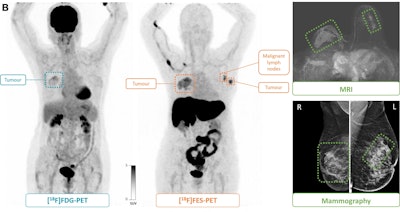

(B) F-18 FDG-PET maximum intensity projection, F-18 FES-PET maximum intensity projection, breast MRI scan, and mammogram in an 81-year-old female participant who presented with a tumor in the right breast. F-18 FES-PET scan shows a second primary tumor (grade 1, lobular) in the left breast and malignant lymph nodes (T2N1M0) that are not visible on the F-18 FDG-PET scan. The tumor in the right breast (T4N0M0, grade 3 ductal carcinoma) is visible on both PET scans. All lesions had also been identified at mammography and MRI. Image and caption courtesy of the RSNA.